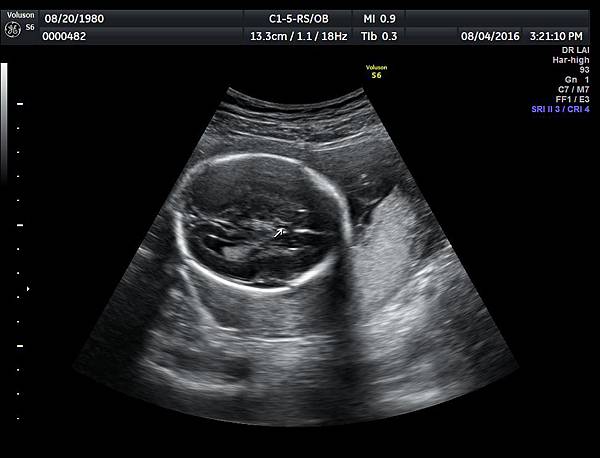

2016年8月4日在執行胎兒高層次超音波檢查時,我發現胎兒腦部的CSP(cavum septum pellucidum)很不清楚(附圖1~4),遇到這種情況,需要仔細評估胎兒腦部的駢胝體,因為CSP的天花板是駢胝體,CSP不明顯時,要合理的懷疑駢胝體沒有發育,或駢胝體下方有長東西(例如lipoma),駢胝體是連接左右大腦的神經纖維所組成。